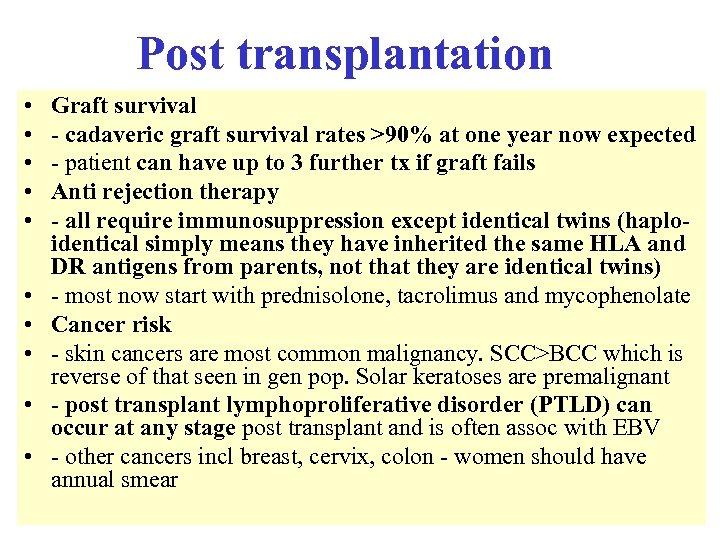

Post transplantation • • • Graft survival - cadaveric graft survival rates >90% at one year now expected - patient can have up to 3 further tx if graft fails Anti rejection therapy - all require immunosuppression except identical twins (haploidentical simply means they have inherited the same HLA and DR antigens from parents, not that they are identical twins) - most now start with prednisolone, tacrolimus and mycophenolate Cancer risk - skin cancers are most common malignancy. SCC>BCC which is reverse of that seen in gen pop. Solar keratoses are premalignant - post transplant lymphoproliferative disorder (PTLD) can occur at any stage post transplant and is often assoc with EBV - other cancers incl breast, cervix, colon - women should have annual smear

Post transplantation • • • Graft survival - cadaveric graft survival rates >90% at one year now expected - patient can have up to 3 further tx if graft fails Anti rejection therapy - all require immunosuppression except identical twins (haploidentical simply means they have inherited the same HLA and DR antigens from parents, not that they are identical twins) - most now start with prednisolone, tacrolimus and mycophenolate Cancer risk - skin cancers are most common malignancy. SCC>BCC which is reverse of that seen in gen pop. Solar keratoses are premalignant - post transplant lymphoproliferative disorder (PTLD) can occur at any stage post transplant and is often assoc with EBV - other cancers incl breast, cervix, colon - women should have annual smear